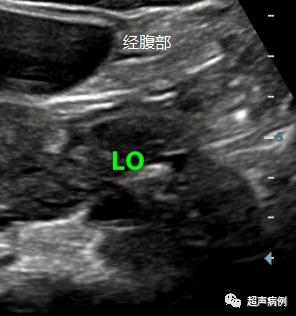

下图就是分别经腹部及经阴道超声的检查对比图。

可以看出经腹部的超声不能看清较小的卵泡及卵巢的细微结构,而经阴道超声就能看得清清楚楚。